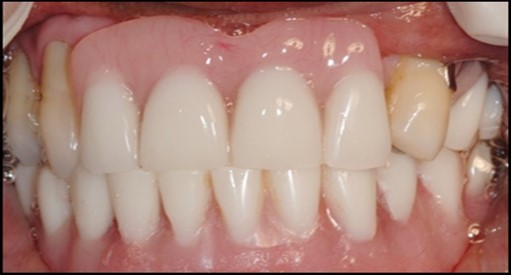

A transferable mark with an indelible pencil is placed on top of each ball abutment and old denture is seated to ideally determine the location for attachment housings. It is followed by preparation of recesses in the intaglio surface of the denture to accommodate the housings (Figure 7B). Lingual vent holes are made for escape of excess acrylic. Placement of nylon processing insert into each of the housings is done with insert seating tool. Figure 8 Seating of the attachment housing onto each ball type abutment is done (Figure 9). Undercuts are blocked out under the housing and soft tissue to prevent acrylic resin from locking the denture onto the abutment. Application of self curing acrylic is done into recessed area and around titanium housings for bonding of the housings to denture. Insertion of denture was done and guiding the patient into proper occlusion with the opposing arch. After the curing of acrylic, denture is removed. Excess acrylic is removed around the housings and lingual vent hole later it is polished (Figure 10). Replace nylon retention insert instead of processing insert into the housings. The insert must seat securely in place and be in level with the housings rim. Overdenture is seated over the ball abutments (Figure 11). Proper instructions have been given to the patient on insertion and removal of prosthesis (Figure 12). The patient was recalled at 1 week, 3 weeks, 3 months, 6 months follow up appointments.

Figure 12.Insertion of the lower denture

Insertion of the lower denture